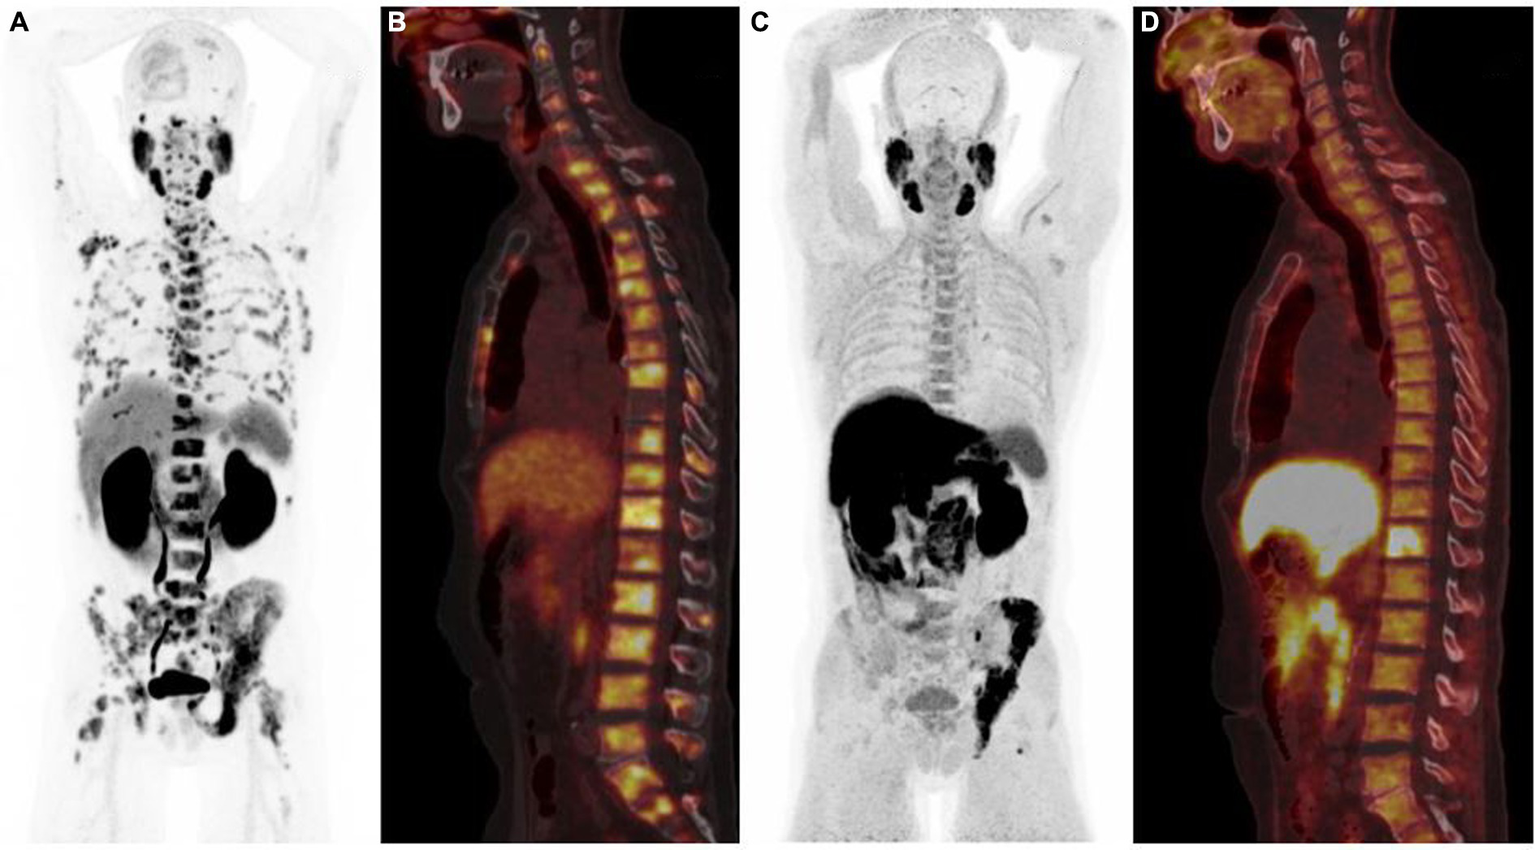

Figure 3

68Ga-PSMA PET/CT [anterior MIP (A), sagittal PET/CT (B)] and 18F-Fluorocholine PET/CT [anterior MIP (C), sagittal PET/CT (D)] illustrating the difference in sensitivity between the two radiotracers, 68Ga-PSMA PET/CT showing more bone metastases than 18F-Fluorocholine scan.